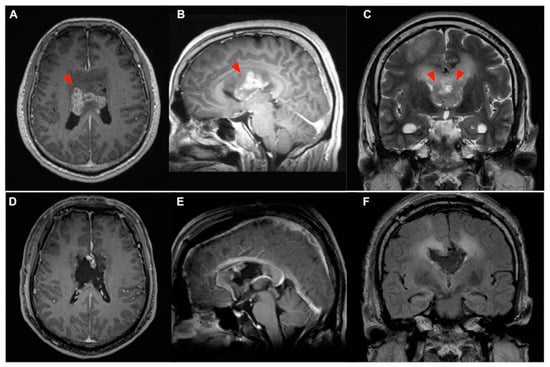

2.1.1. Preoperative Evaluation

2.1.2. Surgical Resection

2.1.3. Postoperative Clinical Course